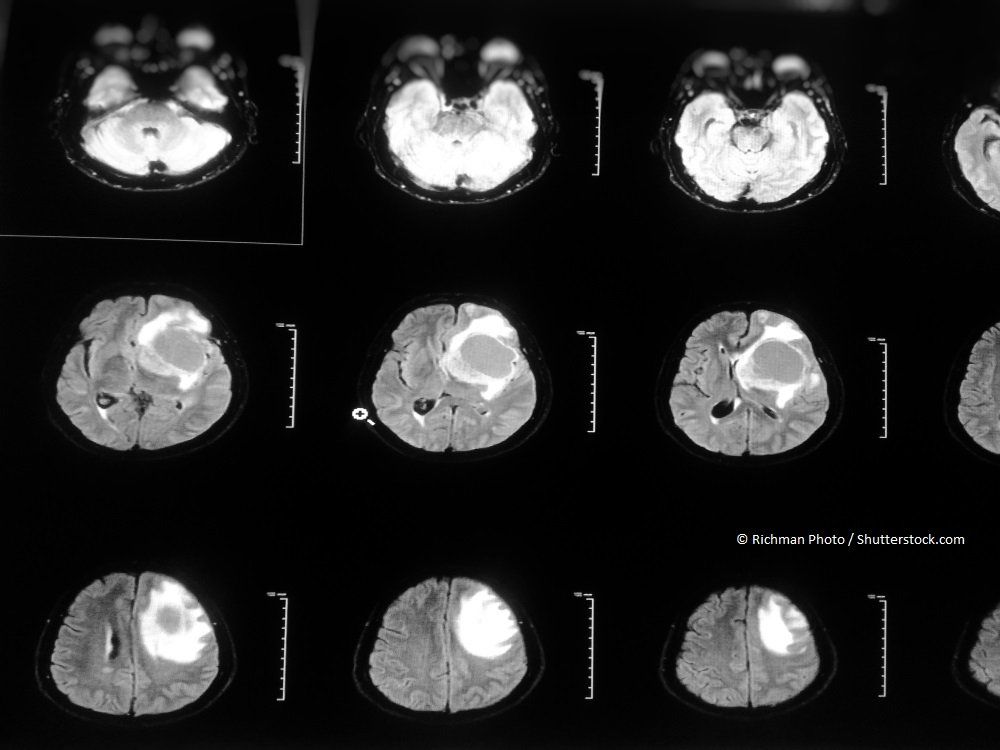

A new study offers hope in predicting glioblastoma responses to chemotherapy, radiation, and combination therapy.

This review focuses on clinical developments and management of newly diagnosed glioblastoma, and includes a discussion about the incorporation of molecular features into the classification of this disease.

MRI-guided laser interstitial thermal therapy appears to be safe and effective for glioblastomas and may add an average of 2 months to life expectancy.